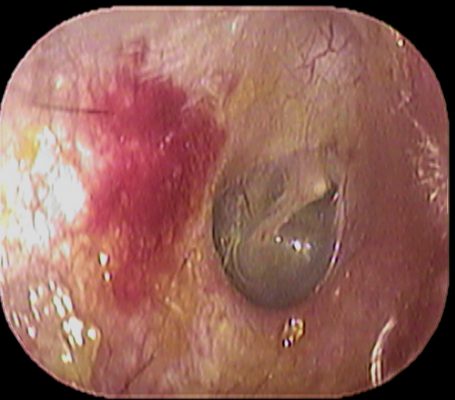

先日当院に受診された患者さんも、来院時は止血していましたが↓

上記の赤丸部分が怪しかったので、擦ってみたところ↓

やはり出血してきました

かなり出血してきたため、電気で凝固することに

当院では

子供の患者さんでも頻回に出血する場合は、積極的に電気凝固しております。

上手く電気凝固出来た場合の止血効果は非常に高いです。

鼻出血で困っておられる患者さんは、耳鼻咽喉科で鼻内のチェックをお勧めいたします